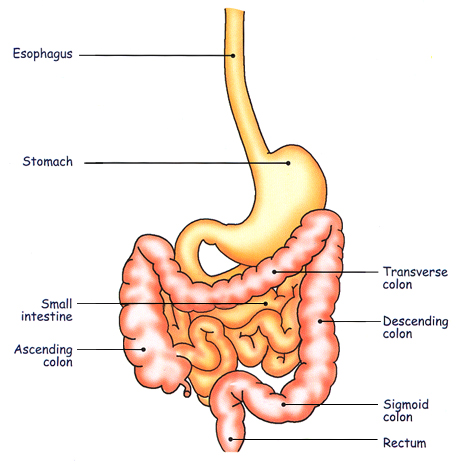

De dag voordien krijgt de patiënt een laxativum

zodat het colon zuiver is |